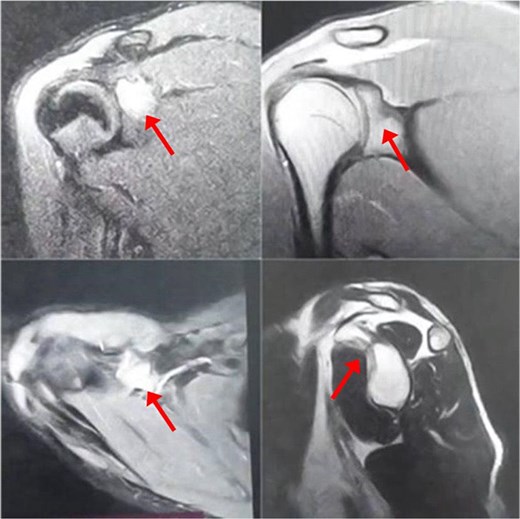

The patient initially underwent conservative treatment with NSAIDs and rest, but symptoms did not improve. As a result, surgical intervention was planned using the deltopectoral approach. The procedure begins with the patient positioned in the beach chair position under general anesthesia. A longitudinal incision is made along the deltopectoral groove, and the cephalic vein is identified and retracted laterally with the deltoid. The deltoid is retracted laterally and the pectoralis major medially to expose the clavipectoral fascia, which is incised to access the coracoid process. Blunt dissection is used to expose the base of the coracoid while avoiding neurovascular structures. Decortication of the coracoid base is performed, followed by biopsy of the lesion (Fig. 3a) and fixation of the coracoid process with a screw (Fig. 3b). An X-ray was performed postoperatively to confirm proper placement of the screw (Fig. 4).

X-ray of the left shoulder post-operatively which shows proper placement of the screw.